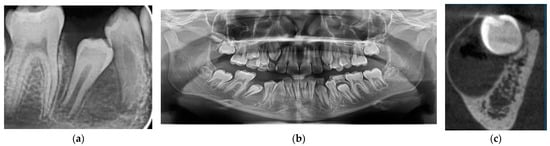

2.2.3. Case 3